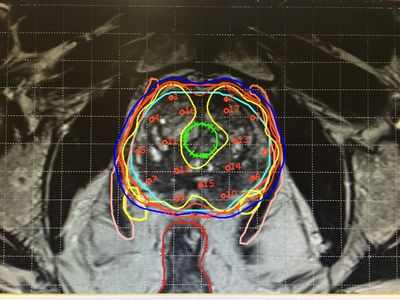

При брахитерапии с высокой мощностью дозы точная доза излучения доставляется к раковым клеткам через катетеры, имплантированные в специально подобранный аппликатор. В отличие от шестинедельной дистанционной лучевой терапии, при которой сеансы лечения могут длиться до шести часов, курс брахитерапии с высокой мощностью дозы включает шесть трехминутных сеансов в течение двух недель.

"Лечение дистанционной лучевой терапией может быть слишком долгим и болезненным для пожилых пациентов," Доктор. Нараяна сказал. "Он также подвергает здоровую ткань вокруг поражения радиации, что может усилить побочные эффекты. Брахитерапия направляет более высокую дозу излучения непосредственно на опухоль, сохраняя при этом здоровые ткани поблизости."